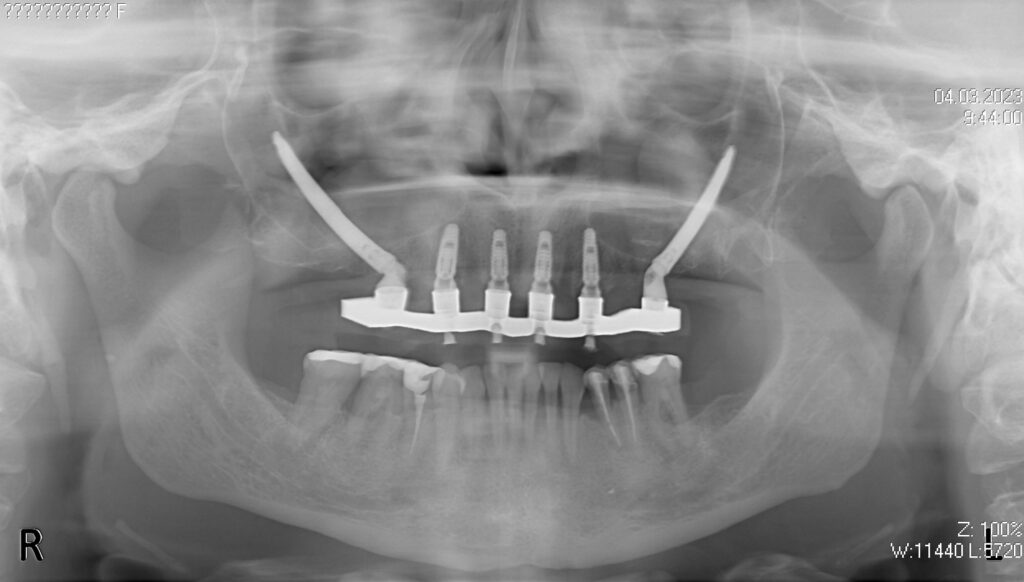

На верхней челюсти были удалены зубы, которые находились в неудовлетворительном состоянии, проведена комплексная имплантация по системе All-on-6, установлены 4 имплантата Megagen AnyOne и 2 скуловых имплантата NeoDent.

Фиксации имплантата внутри костной ткани (торк).

снимок